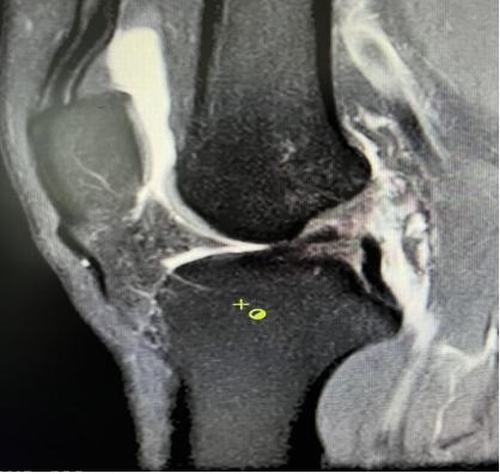

膝關(guān)節(jié)韌帶損傷磁共振

我院骨科三病區(qū)近期收治了4名膝關(guān)節(jié)交叉韌帶損傷患者。25歲的齊先生,因打籃球時不慎扭傷左膝,致右膝腫痛,遂來我院治療;30歲趙先生酷愛足球,扭傷右膝關(guān)節(jié)來我院就診;50歲的張先生、42歲劉先生因騎車滑倒摔傷、膝關(guān)節(jié)腫痛不適、活動受限,收治入院。骨科三病區(qū)李鵬主任團隊詳細查體以及完善影像學檢查后進行診斷:幾位患者共同診斷均有“前交叉韌帶損傷”,不同程度合并有“半月板損傷”、“股骨軟骨損傷”、“內(nèi)側(cè)副韌帶斷裂”。